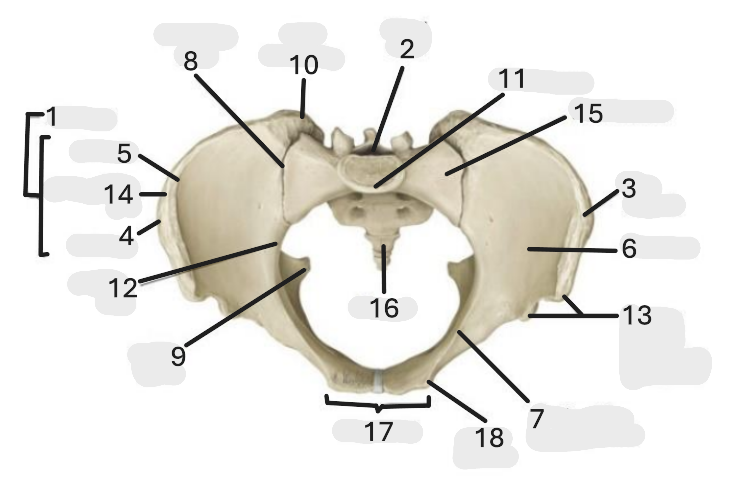

Where is the iliac crest

1

where is the sacral canal

2

Where is the iliac tubercle

3

Where is the outer lip

4

Where is the inner lip

5

Where is the iliac fossa

6

Where is the pectineal line (pecten pubis)

7

Where is the sacroiliac joint

8

Where is the ischial spine

9

Where is the iliac tuberosity

10

Where is the promontory

11

Where is the arcuate line

12

Where is the anterior superior and inferior iliac spine

13

Where is the intermediate line

14

Where is the ala of the sacrum

15

Where is the coccyx

16

Where is the pubic crest

17

Where is the pubic tubercle

18